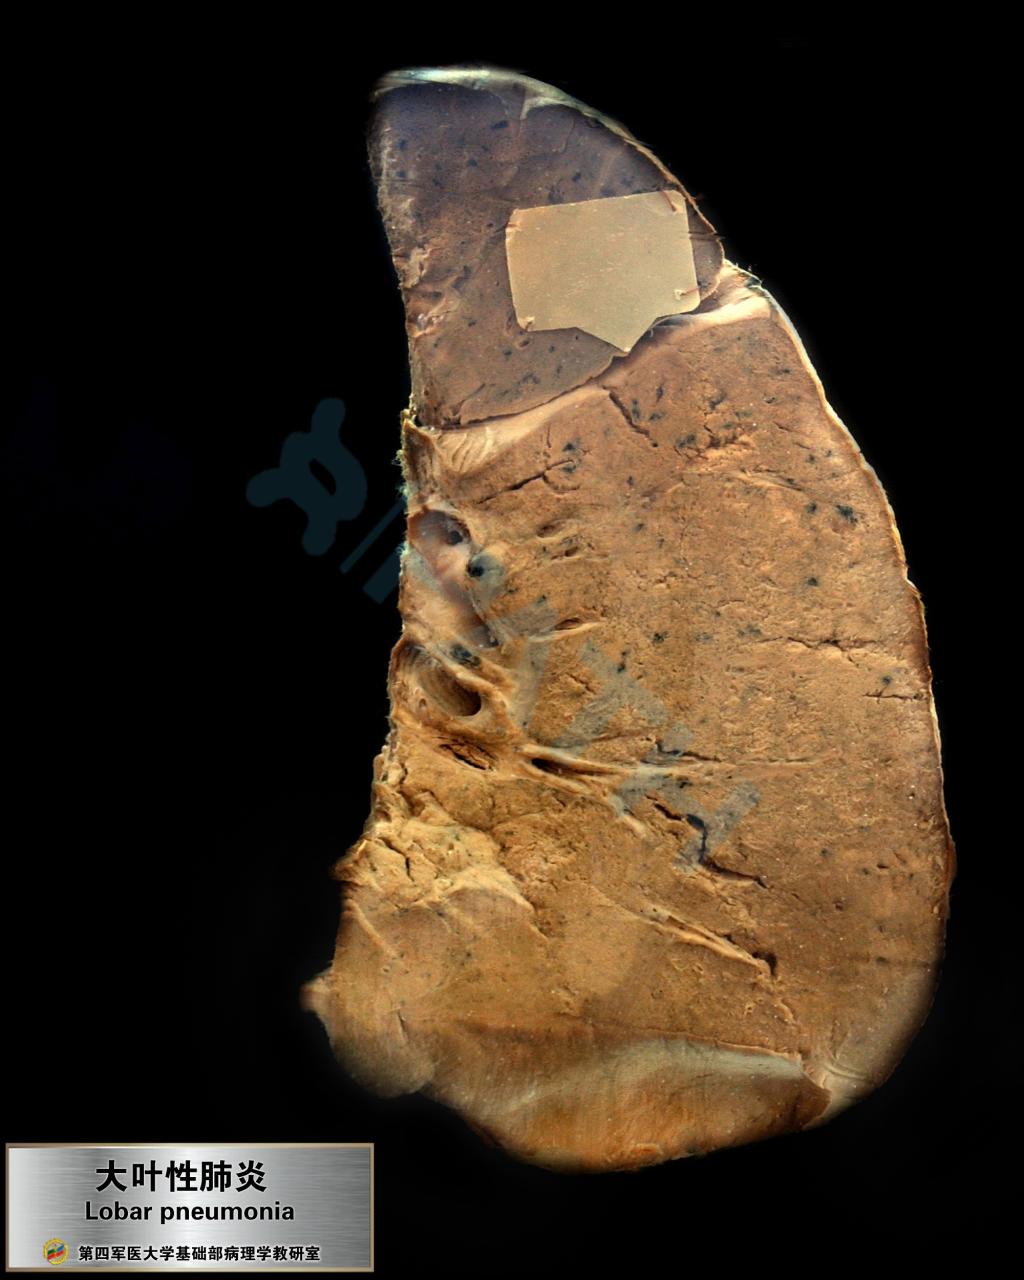

大叶性肺炎